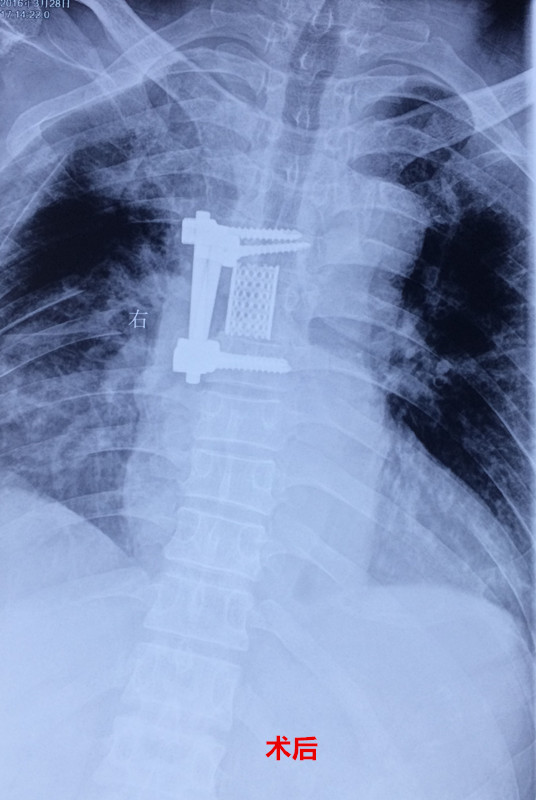

患者入院后,王栋副主任,李锋涛主治医师高度重视,仔细询问患者病情,进行专科查体,分析以往患者的影像学资料,由于肿瘤组织生长巨大,严重压迫右肺,并且已经破坏了胸6椎体及其附件、右侧第6肋骨等,局部结构复杂,为了帮助手术方案的设计,我们采用3D打印技术,术前将肿瘤局部解剖结构打印成3D模型。邀请胸外科张维教授多次会诊,根据3D打印模型制定了详细的手术计划及围手术期治疗方案。经过严密的手术前准备,以王栋副主任、张维教授为主刀、李锋涛主治医师为助手,吴刚副主任医师、罗斌医师为麻醉医师,殷敏、马霞为配合护士,黄亚娟、王芳医师为术中诱发电位监护医师的手术团队努力下,手术顺利完成,成功切除了胸腔内、椎体旁及椎管内肿瘤组织,并进行了脊柱的重建。术后患者恢复良好,很快下肢感觉、肌力恢复,现患者正在康复中。